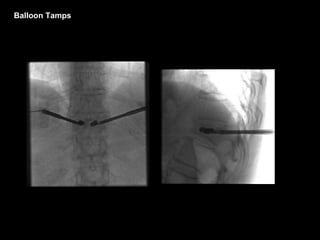

Balloon Tamps